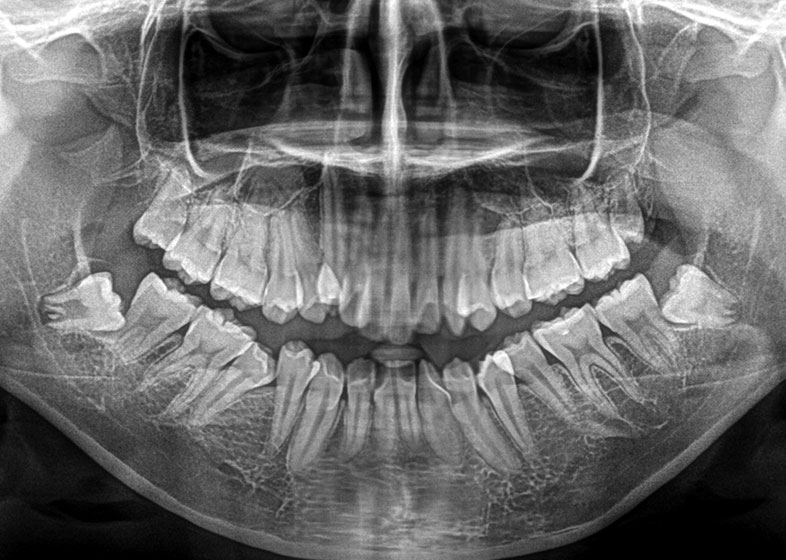

| 年齢 | 19歳 |

|---|---|

| 症状、主訴 | 症状とくになし |

| 治療内容 | 下顎両側埋伏歯抜歯 |

| 費用 | トータル約15,000円 |

| 治療回数 | 5回 |

| メリット | 矯正予定の患者。矯正治療後の歯の後戻りなどを防止出来る。 |

| デメリット | 下顎埋伏歯抜歯については神経麻痺の症状が出る可能性がある。 |

| 院長コメント | 下両側8/まだ10代の子の親知らずの抜歯です。若ければ若いほど抜きやすいです。矯正する為抜歯しました。 |